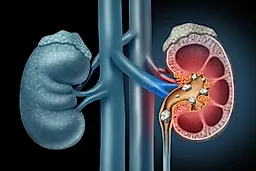

Большинство коралловидных камней обусловлены инфекцией и состоят из аммония и фосфата магния (струвита), а также фосфата кальция. Эти минералы преципи-тируют на матриксную "форму" чашечно-лоханочной системы, имеющую коралловидную конфигурацию. Ведущим патологическим звеном у таких пациентов является хроническое ощелачивание мочи, которое развивается в результате действия уреазообразующих микроорганизмов в моче.

Образование большинства коралловидных камней обусловлено инфекцией. Однако камни мочевой кислоты и цистиновые камни также могут иметь коралловидную конфигурацию. Наиболее часто встречающиеся камни, состоящие из оксалата кальция и фосфата кальция, редко достигают таких размеров и обычно не имеют коралловидной формы.